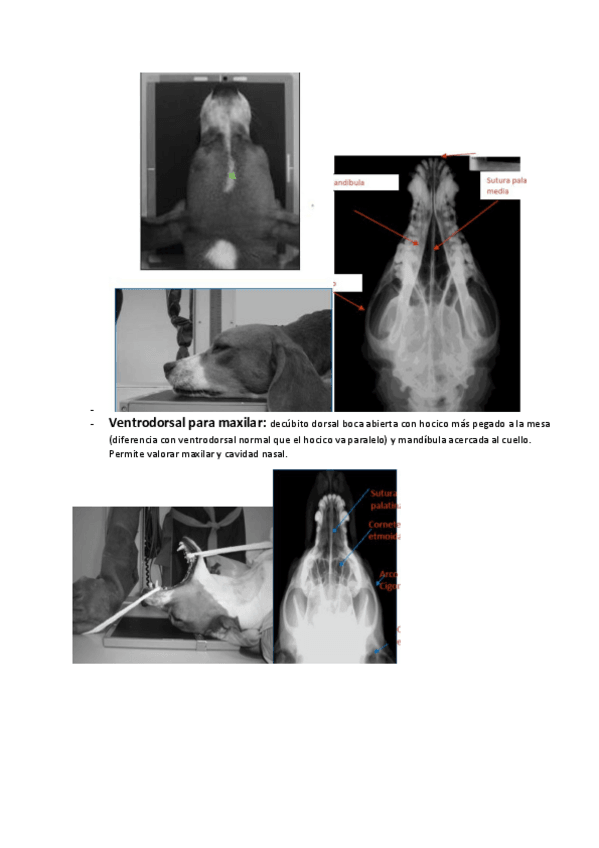

Imágenes de radiografias explicadas

He publicado nuevos apuntes de 3º Diagnóstico Por la Imagen: Imágenes de radiografias explicadas

Rx-equina-1.pdf

Rx-abdomen.pdf

Rx-torax.pdf

Rx-cuello-y-torax.pdf

Rx-miembro-pelviano.pdf

Rx-miembro-anterior.pdf

apuntes